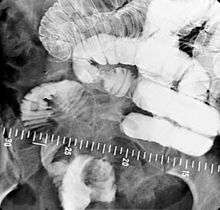

An upper gastrointestinal series, also called an upper gastrointestinal study or contrast radiography of the upper gastrointestinal tract, is a series of radiographs used to examine the gastrointestinal tract for abnormalities. A contrast medium, usually a radiocontrast agent such as barium sulfate mixed with water, is ingested or instilled into the gastrointestinal tract, and X-rays are used to create radiographs of the regions of interest. The barium enhances the visibility of the relevant parts of the gastrointestinal tract by coating the inside wall of the tract and appearing white on the film. This in combination with other plain radiographs allows for the imaging of parts of the upper gastrointestinal tract such as the pharynx, larynx, esophagus, stomach, and small intestine such that the inside wall lining, size, shape, contour, and patency are visible to the examiner. With fluoroscopy, it is also possible to visualize the functional movement of examined organs such as swallowing, peristalsis, or sphincter closure. Depending on the organs to be examined, barium radiographs can be classified into barium swallow, barium meal, barium follow-through, and enteroclysis (small bowel enema). To further enhance the quality of images, air or gas is sometimes introduced into the gastrointestinal tract in addition to barium, and this procedure is called double-contrast imaging. In this case the gas is referred to as the negative contrast medium. Traditionally the images produced with barium contrast are made with plain-film radiography, but computed tomography is also used in combination with barium contrast, in which case the procedure is called CT enterography.[1]

Various types of barium X-ray examinations are used to examine different parts of the gastrointestinal tract. These include barium swallow, barium meal, barium follow-through, and barium enema.[2] The barium swallow, barium meal, and barium follow-through are together also called an upper gastrointestinal series (or study), whereas the barium enema is called a lower gastrointestinal series (or study).[3] In upper gastrointestinal series examinations, the barium sulfate is mixed with water and swallowed orally, whereas in the lower gastrointestinal series (barium enema), the barium contrast agent is administered as an enema through a small tube inserted into the rectum.[2]

Barium sulfate is swallowed, which because it is a radio opaque substance does not allow the passage of X-rays. As a result, areas coated by barium sulfate will appear white on an X-ray film. The passage of barium through the gastrointestinal tract is observed by a radiologist using a fluoroscope attached to a TV monitor. The radiologist takes a series of individual X-ray images at timed intervals depending on the areas to be studied. Sometimes medication which produces gas in the gastrointestinal tract is administered together with the Barium sulfate. This gas distends the gastrointestinal lumen, providing better imaging conditions and in this case the procedure is called double-contrast imaging.[8]